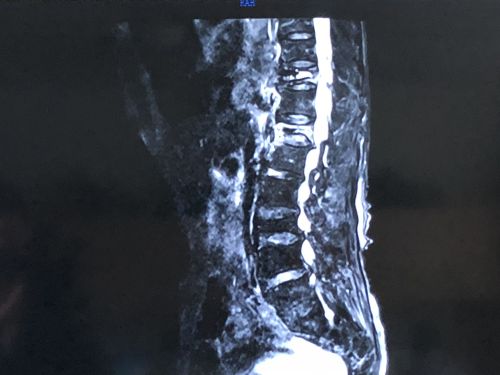

核磁显示,胸椎t10陈旧性骨折不愈合、t12新发压缩性骨折、腰l3陈旧性压缩性骨折。

入院进一步完善CT、核磁等检查后,老人被诊断为“胸椎T10陈旧性骨折不愈合、T12新发压缩性骨折、腰L3陈旧性压缩性骨折,重度骨质疏松症”。由于老人疼痛、活动受限症状典型,手术指征明确,10月16日,刘宏哲副主任医师和常磊主治医师等在局麻下为老人施行皮球囊扩张椎体后凸成形术(ercutaneous